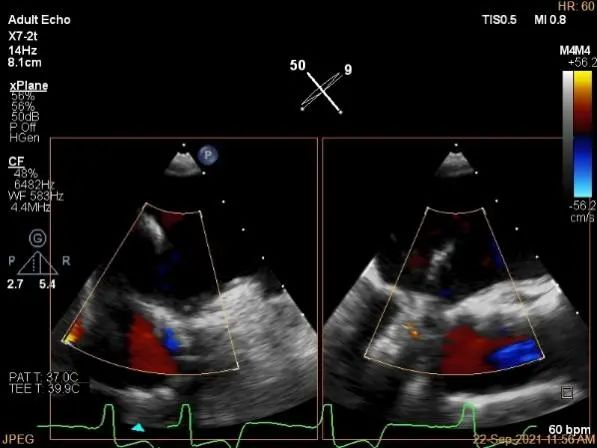

术中超声

P2区脱垂,宽14.8mm,Gap:3.3mm

3D-color,返流重度,3+级

麻醉状态下左肺静脉血流频谱

MVA:6.67cm²